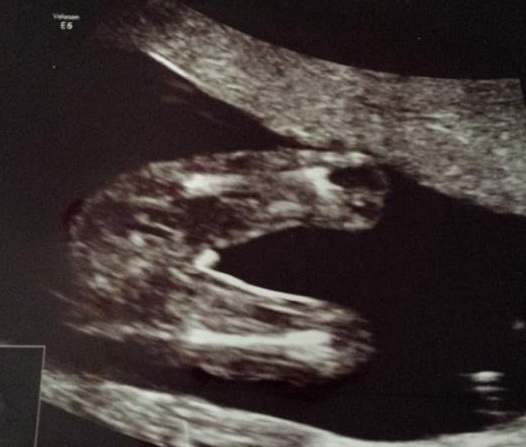

Not the clearest but maybe boy. How many weeks were you? x

16 weeks hun

Poss boy but not really clear enough to tell either way and legs are too clIse together to say for sure

I'm leaning girl.